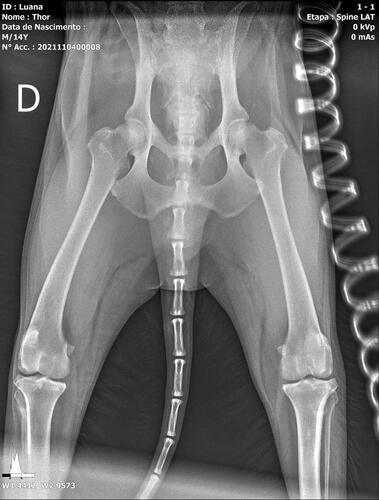

Thor é um senhorzinho que sofre com a síndrome da cauda equina, que é uma doença grave causada pela compressão e inflamação do feixe de nervos na parte inferior do canal vertebral. A gravidade se dá ao fato de poder resultar em paralisia, incontinência intestinal / urinária e a outros problemas de sensibilidade e perda de movimento.

Thor já apresenta todos os sintomas e precisa passar por procedimentos veterinários, necessita de fisioterapia para estimular o retorno do controle esfincteriano (válvula urinária e fecal) e medicações. Uma cirurgia também pode ser o caminho de acordo com o neurologista veterinário.